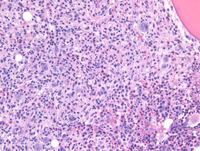

CHL involving marrow, medium and high power

At medium power (left image), scattered large mononuclear (Hodgkin) variants are noted amidst a background rich in histiocytes. At high magnification (image on right), several scattered eosinophils are noted in the background in addition to singly scattered Hodgkin/Reed-Sternberg cells with prominent eosinophilic nucleoli.